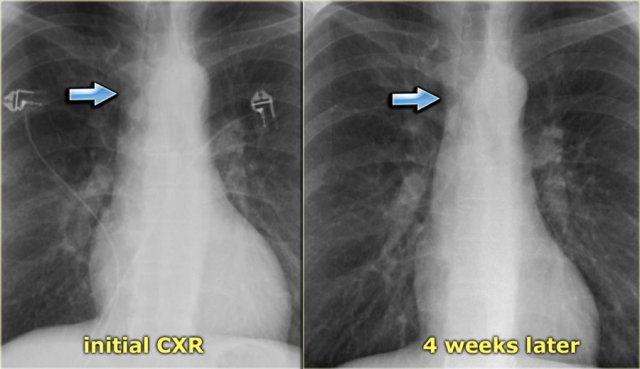

Subtle increased width of vascular pedicle (left) and normalisation (right) Subtle increased width of vascular pedicle (left) and normalisation (right)

On the left a patient with subtle signs of congestive heart failure on the initial chest x-ray (image 1/2).

There is a slightly enlarged vascular pedicle, which becomes more obvious when you compare to the chest film after diuretic therapy (image 2/2).